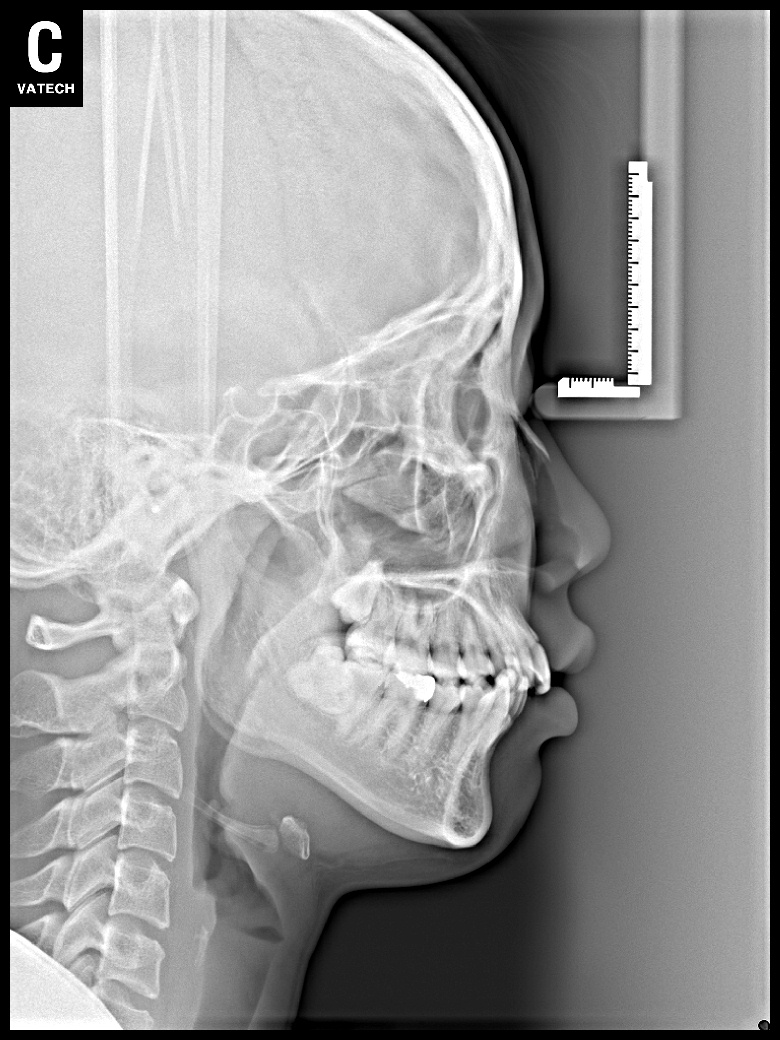

치료 후 사진입니다.